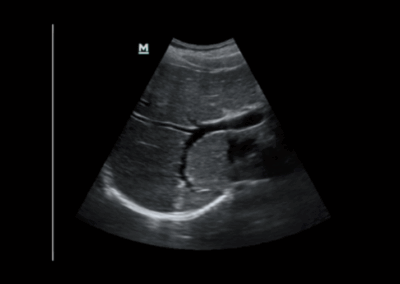

Z60

Sistema de diagnóstico ecográfico.

El sistema Z60 es una buena opción para aquellos que requieren un rendimiento de imagen de alta calidad, una movilidad simple y asequibilidad cuando se trata de imágenes ecográficas avanzadas. Con configuraciones completas y un diseño integrado, el Z60 es el resultado de los esfuerzos continuos y decididos de Mindray para hacer que la atención médica primaria sea más eficiente, eficaz y accesible para todos.